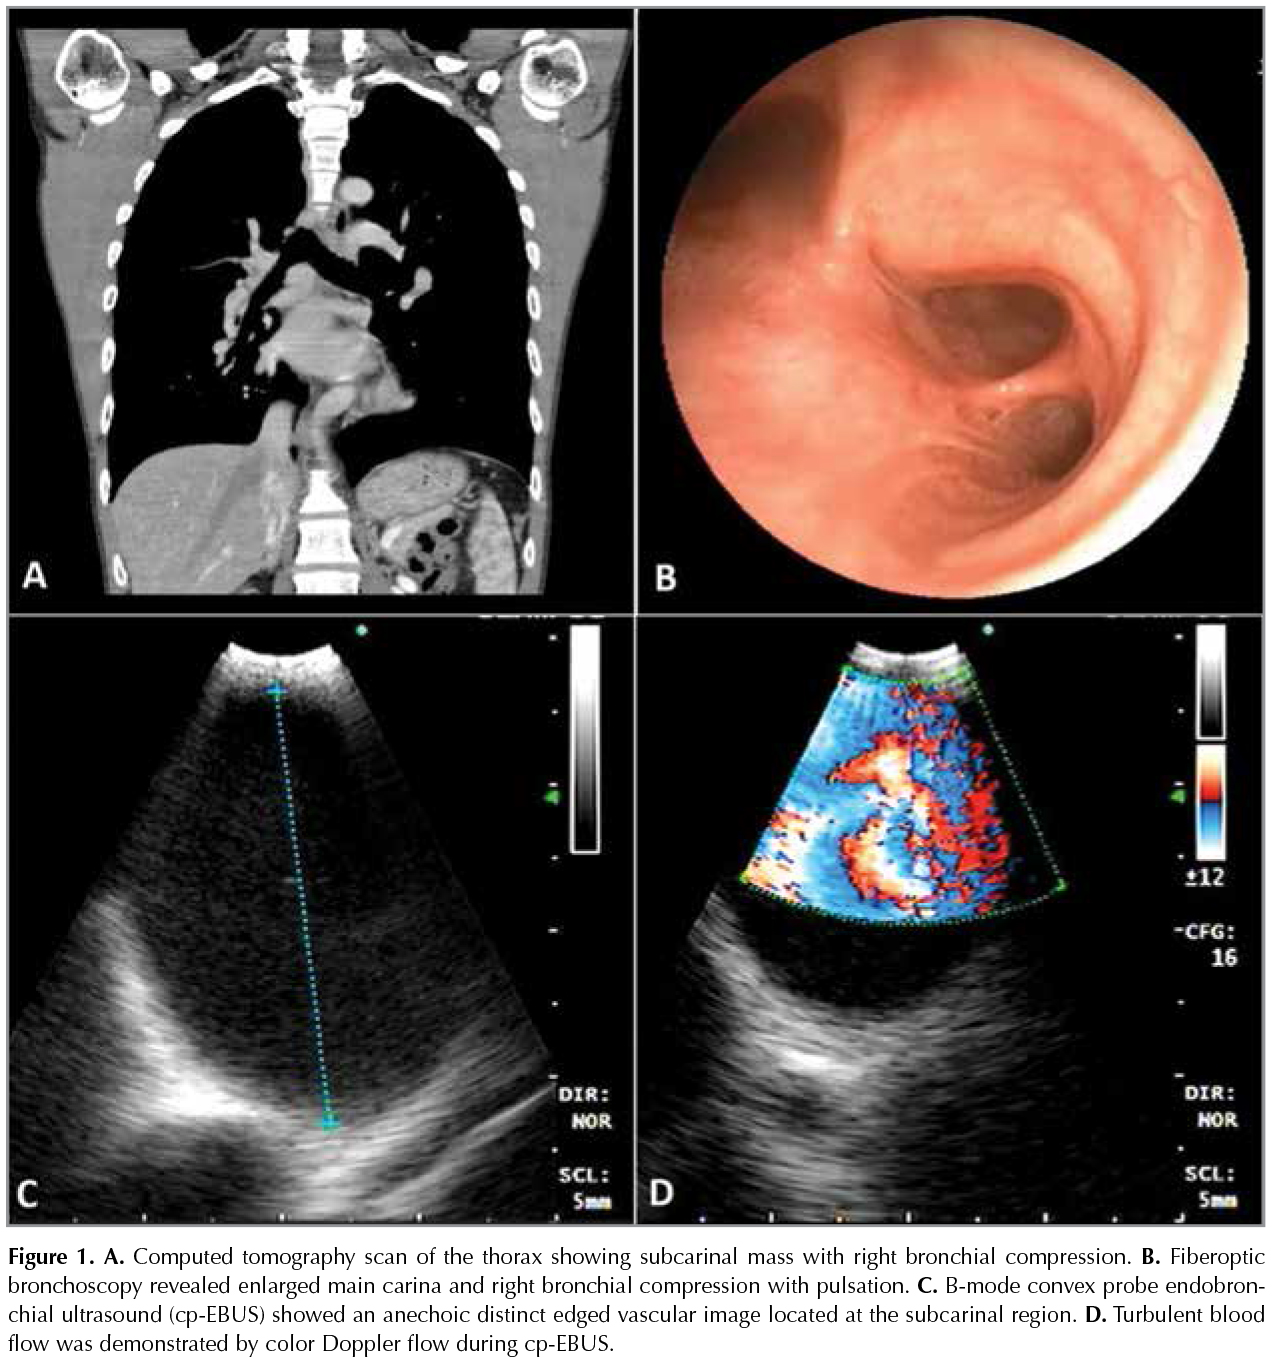

A 45 year-old male without known chronical diseases presented to our chest diseases clinic with a complaint of productive cough for 2 weeks. On his physical examination, vital signs were in normal limits. Respiratory crackles were heard during inspiration on right lower lung zone. Other system examinations were normal. Laboratory test was also in normal limits. Postero-anterior (PA) chest X-Ray showed right hilar enlargement. Non-contrast enhanced computed tomography (CT) revealed a well marginated lesion that was located at the subcarinal region and pulmonary infiltration located on the posterior segment of the right lower lobe (Figure 1A). Antibiotics with amoxicillin clavulonate 1000 mg bid and clarithromycin 500 mg bid were prescribed for treatment of pneumonia. Fiberoptic bronchoscopy was performed for diagnosis of subcarinal lesion. Bronchoscopy revealed a pulsatile enlargement on main carina through the right main bronchus (Figure 1B). Convex probe endobronchial ultrasound (cp-EBUS) was also performed to visualize this pulsatile lesion. EBUS revealed a distinct edged anechoic vascular lesion (Figure 1C). Color Doppler flow was verified the turbulent blood flow within this lesion (Figure 1D). Then, new contrasted computed tomography pulmonary angiography (CTPA) was employed to demonstrate this vascular anomaly with the differential diagnosis of pulmonary artery aneurysm (PAA). Right PAA located at the subcarinal region was exactly diagnosed and visualized after tomography images (Figure 2A-B). No additional comorbid situation associated with PAA was observed during echocardiography. Follow-up of patient was planned for PAA related complications (eg. hemoptysis, huge dilatation etc.).

Figure 1A-D

Pulmonary artery aneurysms are uncommon and rarely misdiagnosed on non-or poorly contrast enhanced CT images (1,2). Cp-EBUS and color doppler flow can be a useful technique to differentiate vascular lesions from lymph nodes and masses (2). Hence, cp-EBUS can help to avoid further investigations resulting in disastrous complications.